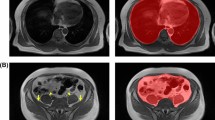

Fully automated abdominal adipose tissue segmentation from computed tomography (CT) scans plays an important role in biomedical diagnoses and prognoses. However, to identify and segment subcutaneous adipose tissue (SAT) and visceral adipose tissue (VAT) in the abdominal region, the traditional routine process used in clinical practise is unattractive, expensive, time-consuming and leads to false segmentation. To address this challenge, this paper introduces and develops an effective global-anatomy-level convolutional neural network (ConvNet) automated segmentation of abdominal adipose tissue from CT scans termed EFNet to accommodate multistage semantic segmentation and high similarity intensity characteristics of the two classes (VAT and SAT) in the abdominal region.

EFNet consists of three pathways: (1) The first pathway is the max unpooling operator, which was used to reduce computational consumption. (2) The second pathway is concatenation, which was applied to recover the shape segmentation results. (3) The third pathway is anatomy pyramid pooling, which was adopted to obtain fine-grained features. The usable anatomical information was encoded in the output of EFNet and allowed for the control of the density of the fine-grained features.

We formulated an end-to-end manner for the learning process of EFNet, where the representation features can be jointly learned through a mixed feature fusion layer. We immensely evaluated our model on different datasets and compared it to existing deep learning networks. Our proposed model called EFNet outperformed other state-of-the-art models on the segmentation results and demonstrated tremendous performances for abdominal adipose tissue segmentation.

EFNet is extremely fast with remarkable performance for fully automated segmentation of the VAT and SAT in abdominal adipose tissue from CT scans. The proposed method demonstrates a strength ability for automated detection and segmentation of abdominal adipose tissue in clinical practise.